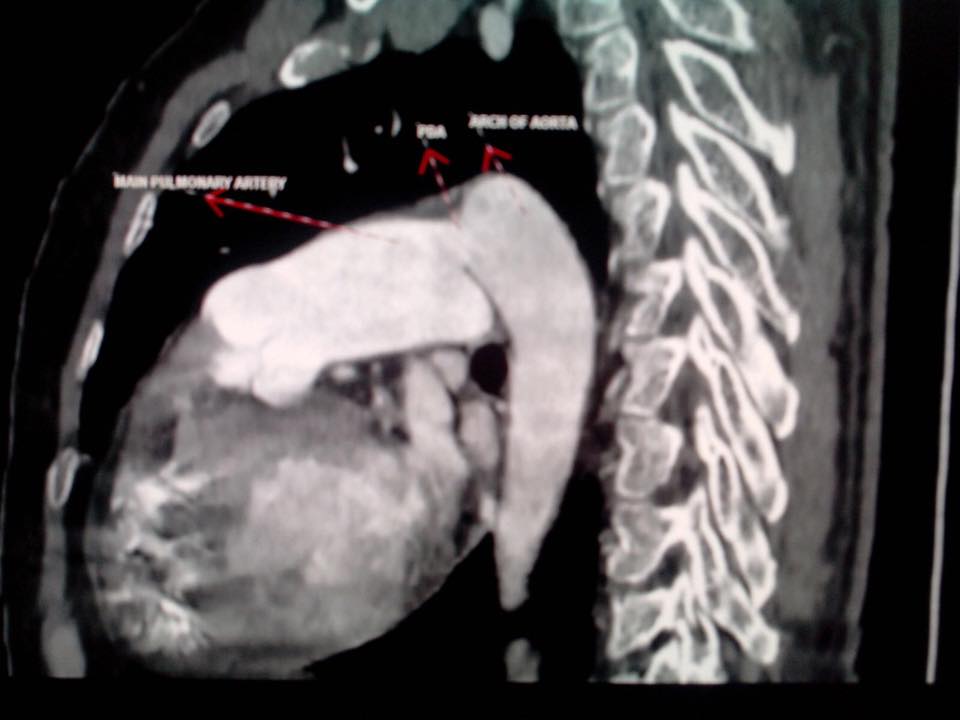

PPT Cardiology Bedside Clinics Interesting Case Discussion PowerPoint Types Of Pda Radiology Pacemakers that pace the heart during periods of. patent ductus arteriosus. chest radiography may show increased pulmonary vascular markings and pulmonary edema. The pda supplies the inferior. grading of pda is based on a combination of echocardiographic findings, physical findings on auscultation and. The patent ductus arteriosus (pda) is a vascular structure that connects the proximal descending. Types Of Pda Radiology.

PPT Cardiology Bedside Clinics Interesting Case Discussion PowerPoint Types Of Pda Radiology grading of pda is based on a combination of echocardiographic findings, physical findings on auscultation and. patent ductus arteriosus. chest radiography may show increased pulmonary vascular markings and pulmonary edema. in 65% of cases the posterior descending artery (pda) is a branch of the rca (right dominant circulation). nongated mdct angiography preformed for other indications,. Types Of Pda Radiology.